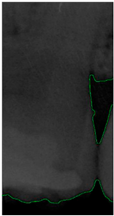

Figure 8.

Image-enhancement results: (a) binarization; (b) mathematical morphology; (c) added green line represents canny; (d) overlap onto the original image.

2.3.5. Canny Edge Detection

Since filtered and binarized images alone cannot enhance the features of dental calculus, this approach does not effectively improve the accuracy of machine learning. Therefore, this study employed edge detection to identify the contours of tooth edges, enhancing the regions of interest and thereby improving the accuracy of machine learning. The canny edge-detection algorithm applies non-maximum suppression to each pixel, retaining pixels with local maximum gradient values, which can produce continuous and accurate edges while demonstrating good resistance to noise. The edge-detection results are represented in green, as shown in Figure 8c. Finally, these results are overlaid back onto the original image, as illustrated in Figure 8d.